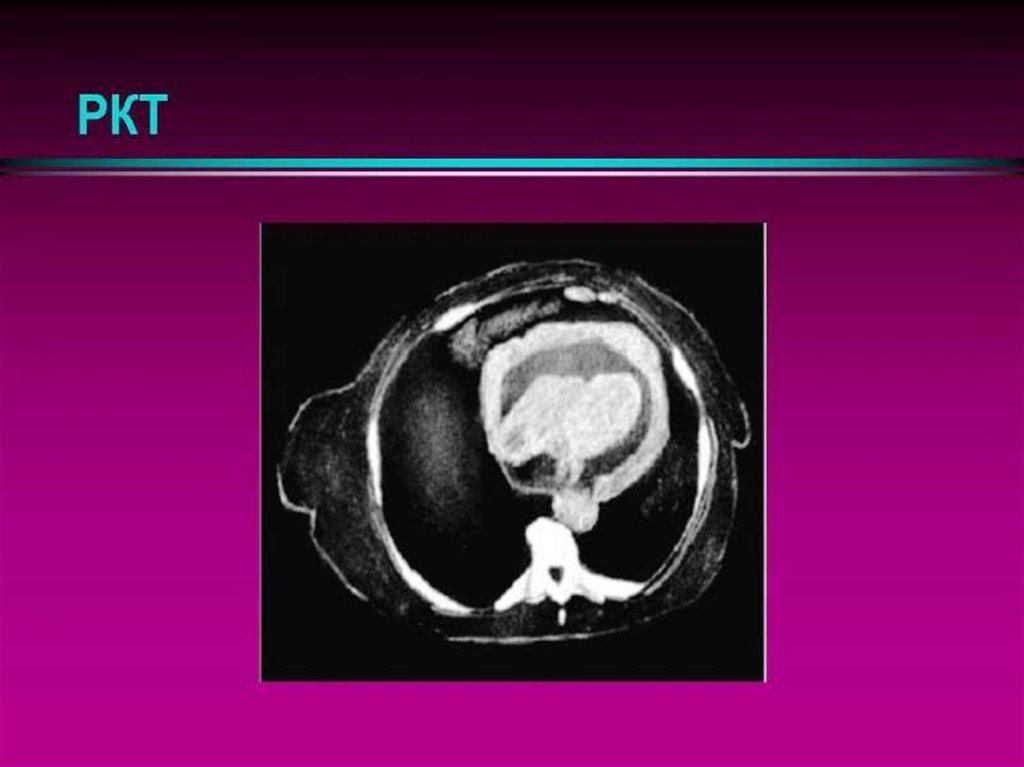

3. Клинико-морфологичекая классификация перикардитов

III. Хронические (более 6 месяцев от начала заболевания):

Констриктивный:

▪ с обызвествлением (“панцирное сердце”):